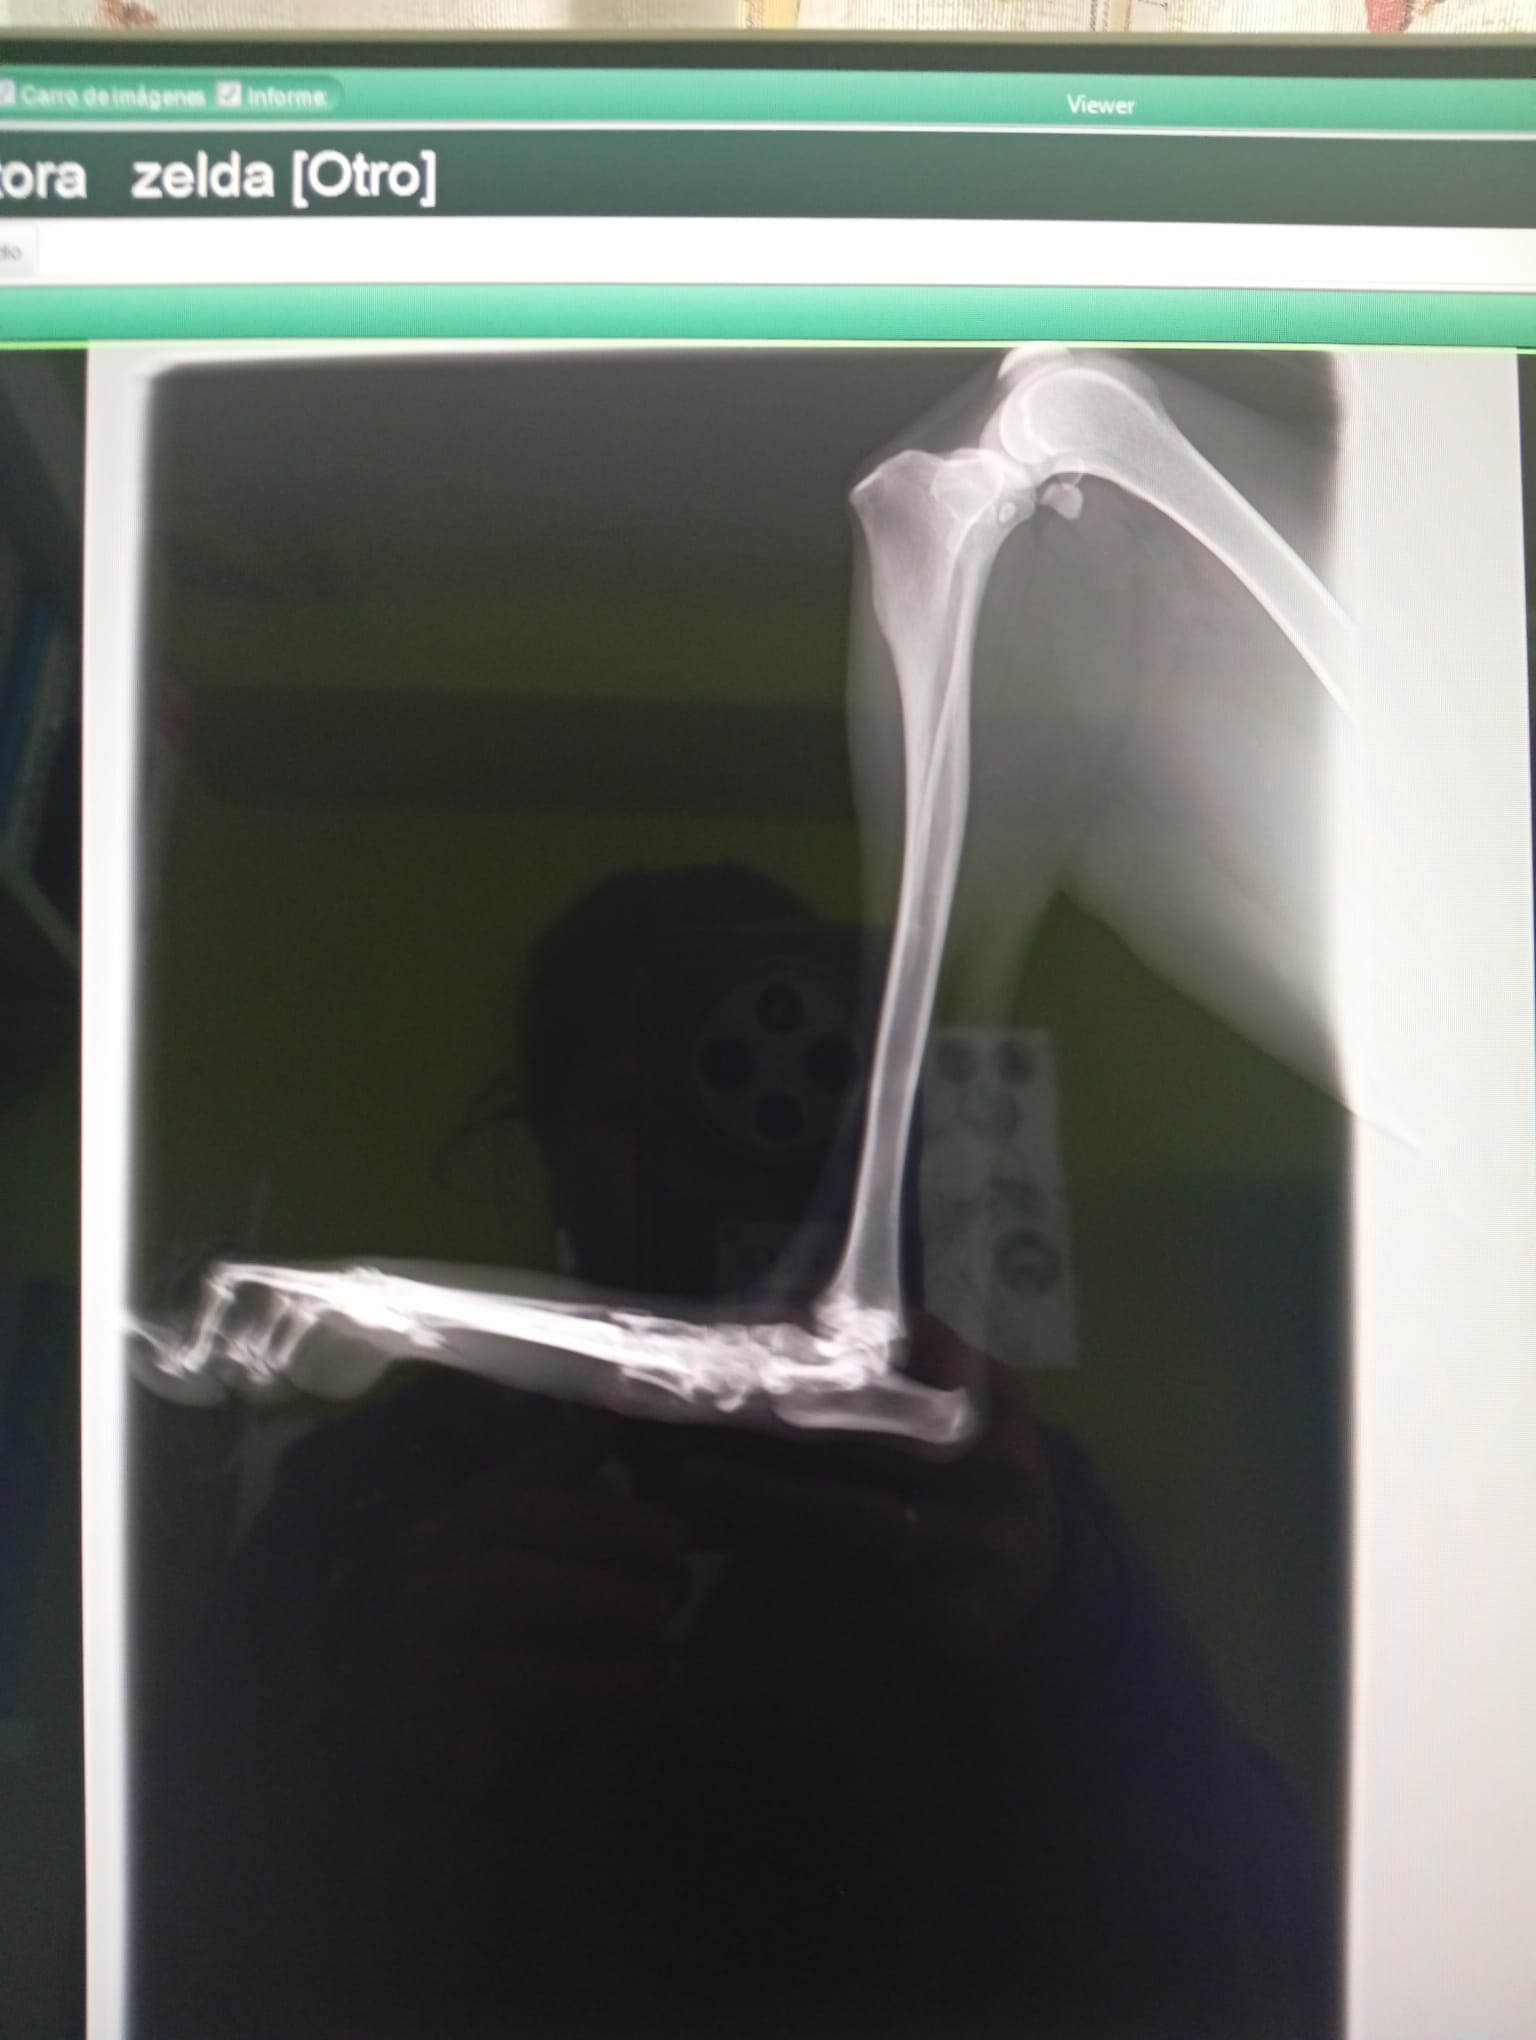

Zelda es una galguita mayor sin chip, que por las evidencias de su cuerpo no ha tenido buena vida. Tras visita a la veterinaria y rx , tiene los dedos de la pata «machacados».